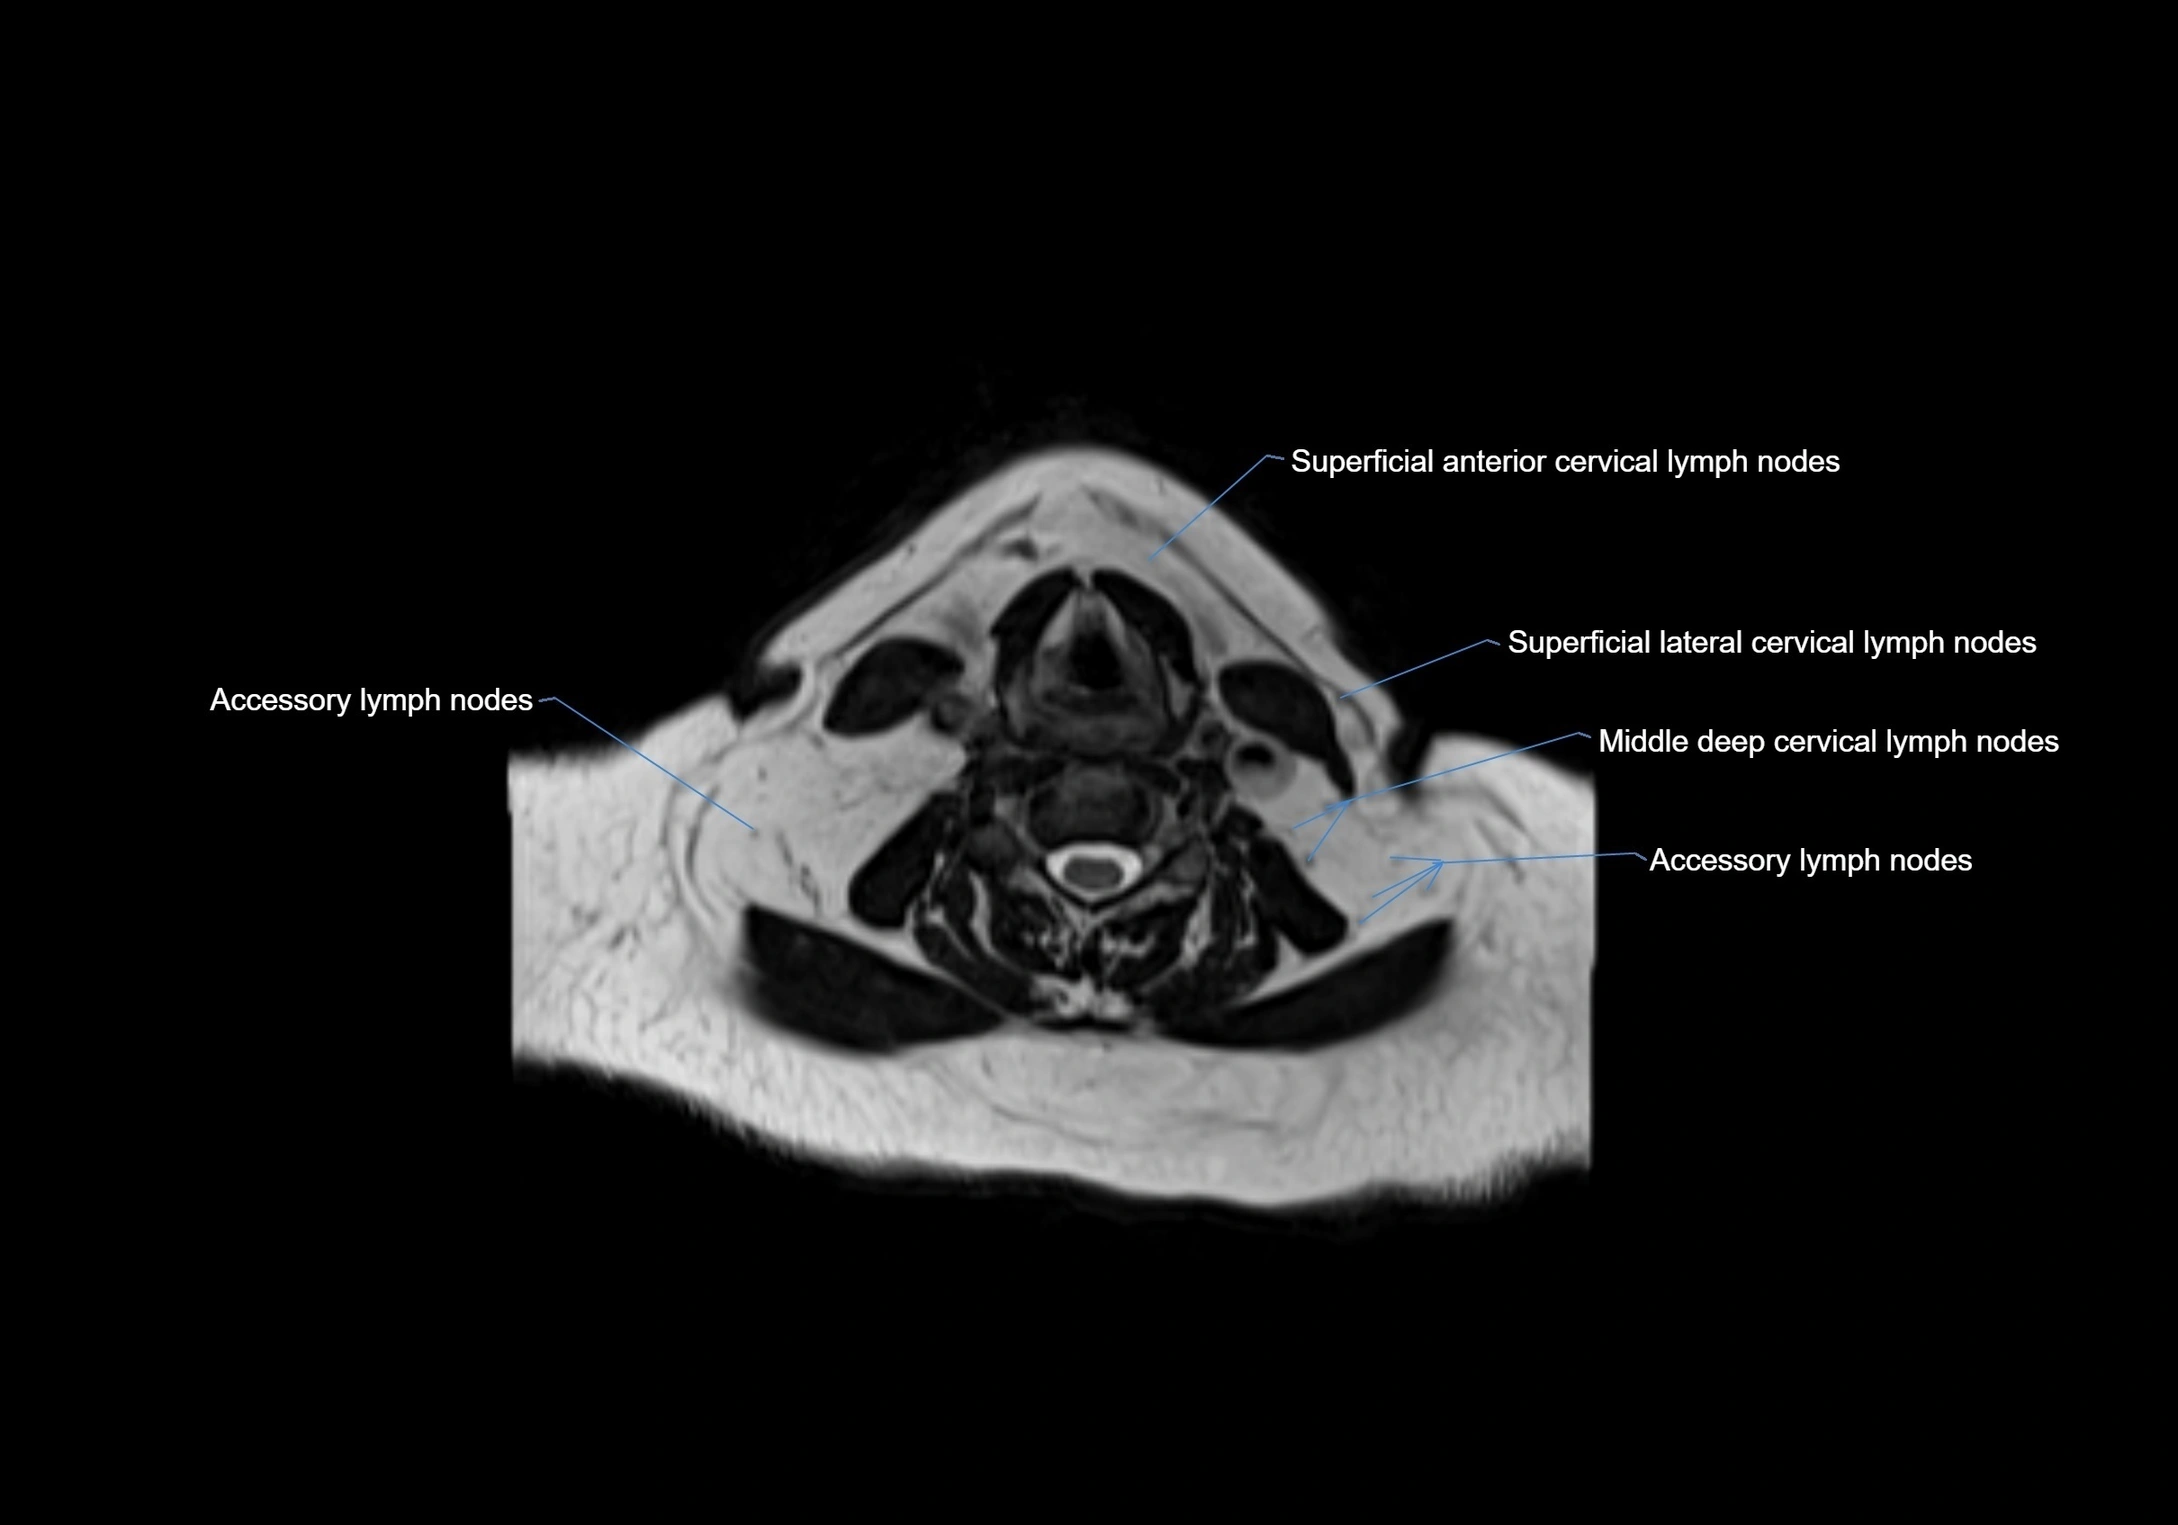

Accessory lymph nodes are small, secondary lymph nodes located along the main facial and cervical lymphatic chains, often adjacent to primary lymph nodes, such as preauricular, submandibular, or occipital nodes. They are typically less than 5 mm in diameter, embedded within subcutaneous fat or connective tissue, and may be variable in number and location. These nodes provide additional filtration and immune surveillance for lymph collected from the face, scalp, and neck regions. Accessory lymph nodes are usually non-palpable in healthy individuals but may enlarge in response to infection, inflammation, or metastasis, making them clinically significant.

• Found along primary lymph node chains, including preauricular, submandibular, parotid, and occipital regions

• Embedded in subcutaneous fat or superficial fascia, often lateral or posterior to primary nodes

• Variable in number; may occur unilaterally or bilaterally, depending on individual anatomy